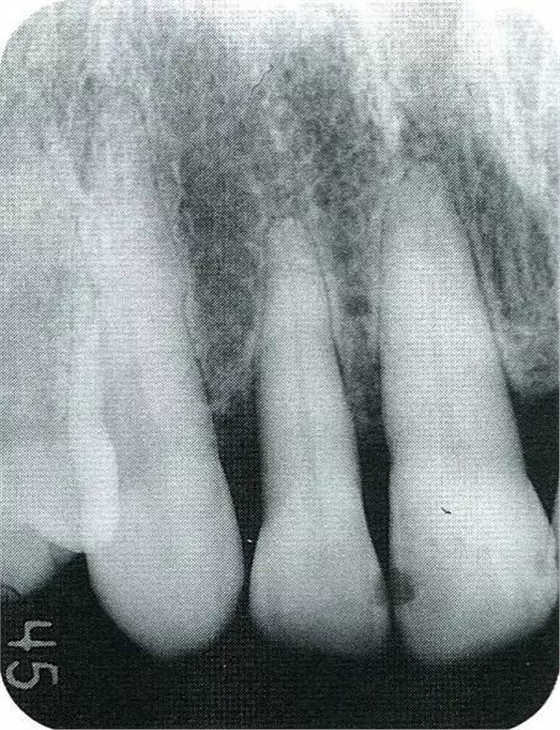

▲圖7-2術(shù)前x片。確認(rèn)存在垂直性深骨缺損。